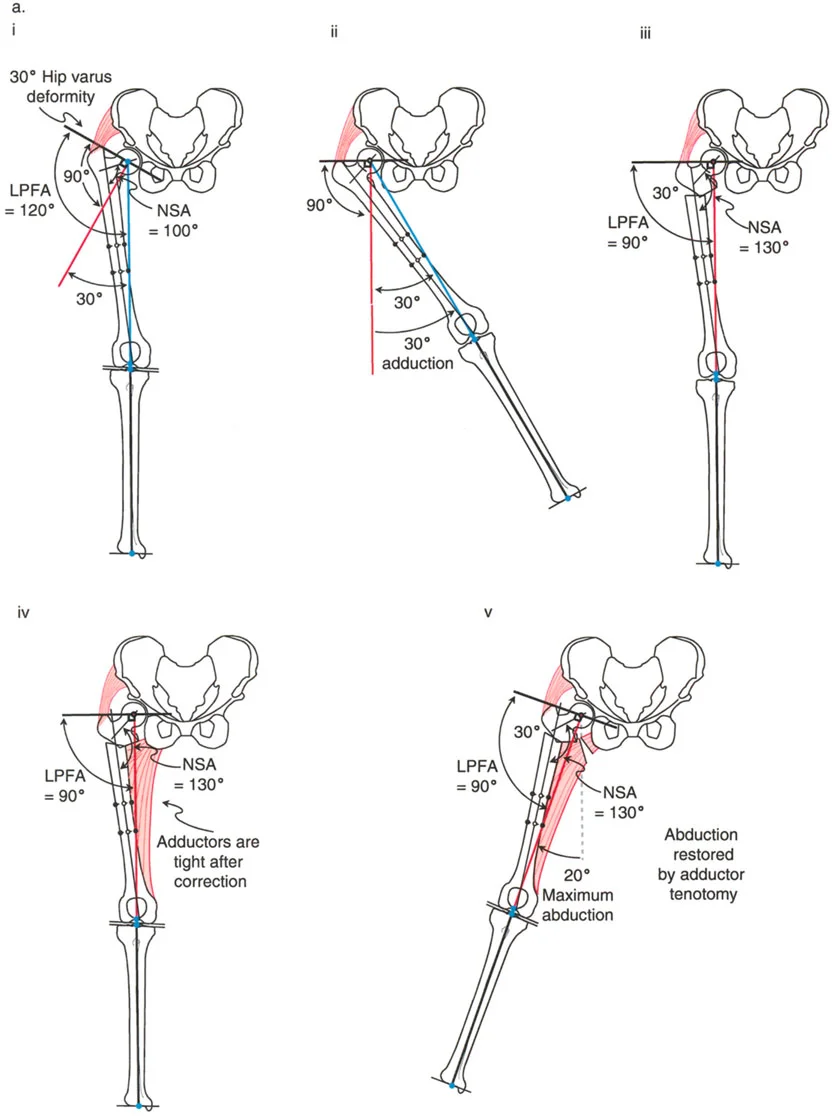

لا يقتصر فهم تفاوت طول الأطراف على مجرد قياسات بسيطة؛ بل يتطلب فهمًا عميقًا ثلاثي الأبعاد لميكانيكا الأطراف السفلية الحيوية، ومبادئ بالي لتصحيح التشوهات – بما في ذلك انحراف المحور الميكانيكي (MAD) ومركز دوران الزاوية (CORA) – واتخاذ قرارات دقيقة ومناسبة لكل مريض بشأن أساليب التصحيح التدريجي مقابل التصحيح الحاد.

تفاوت طول الأطراف ليس مجرد تشخيص معزول؛ إنه تشوه معقد ومتعدد الأبعاد يُعرّف أساسًا بمعيارين مميزين: المقدار والاتجاه. عدم أخذ كلا المعيارين في الاعتبار يؤدي حتمًا إلى سوء محاذاة جراحية ونتائج سلبية للمريض.

- الاتجاه: يشير إلى طبيعة التفاوت – ما إذا كانت المشكلة الأساسية هي القصر أو النمو الزائد، والأهم من ذلك، كيف يتفاعل هذا التفاوت في الطول مع التشوهات الزاوية المصاحبة (مثل التقوس للداخل أو الخارج، أو الانحناء الأمامي أو الخلفي) أو التشوهات الانتقالية. نادرًا ما يكون العظم "قصيرًا" فقط؛ غالبًا ما يكون قصيرًا ومنحنيًا في آن واحد.